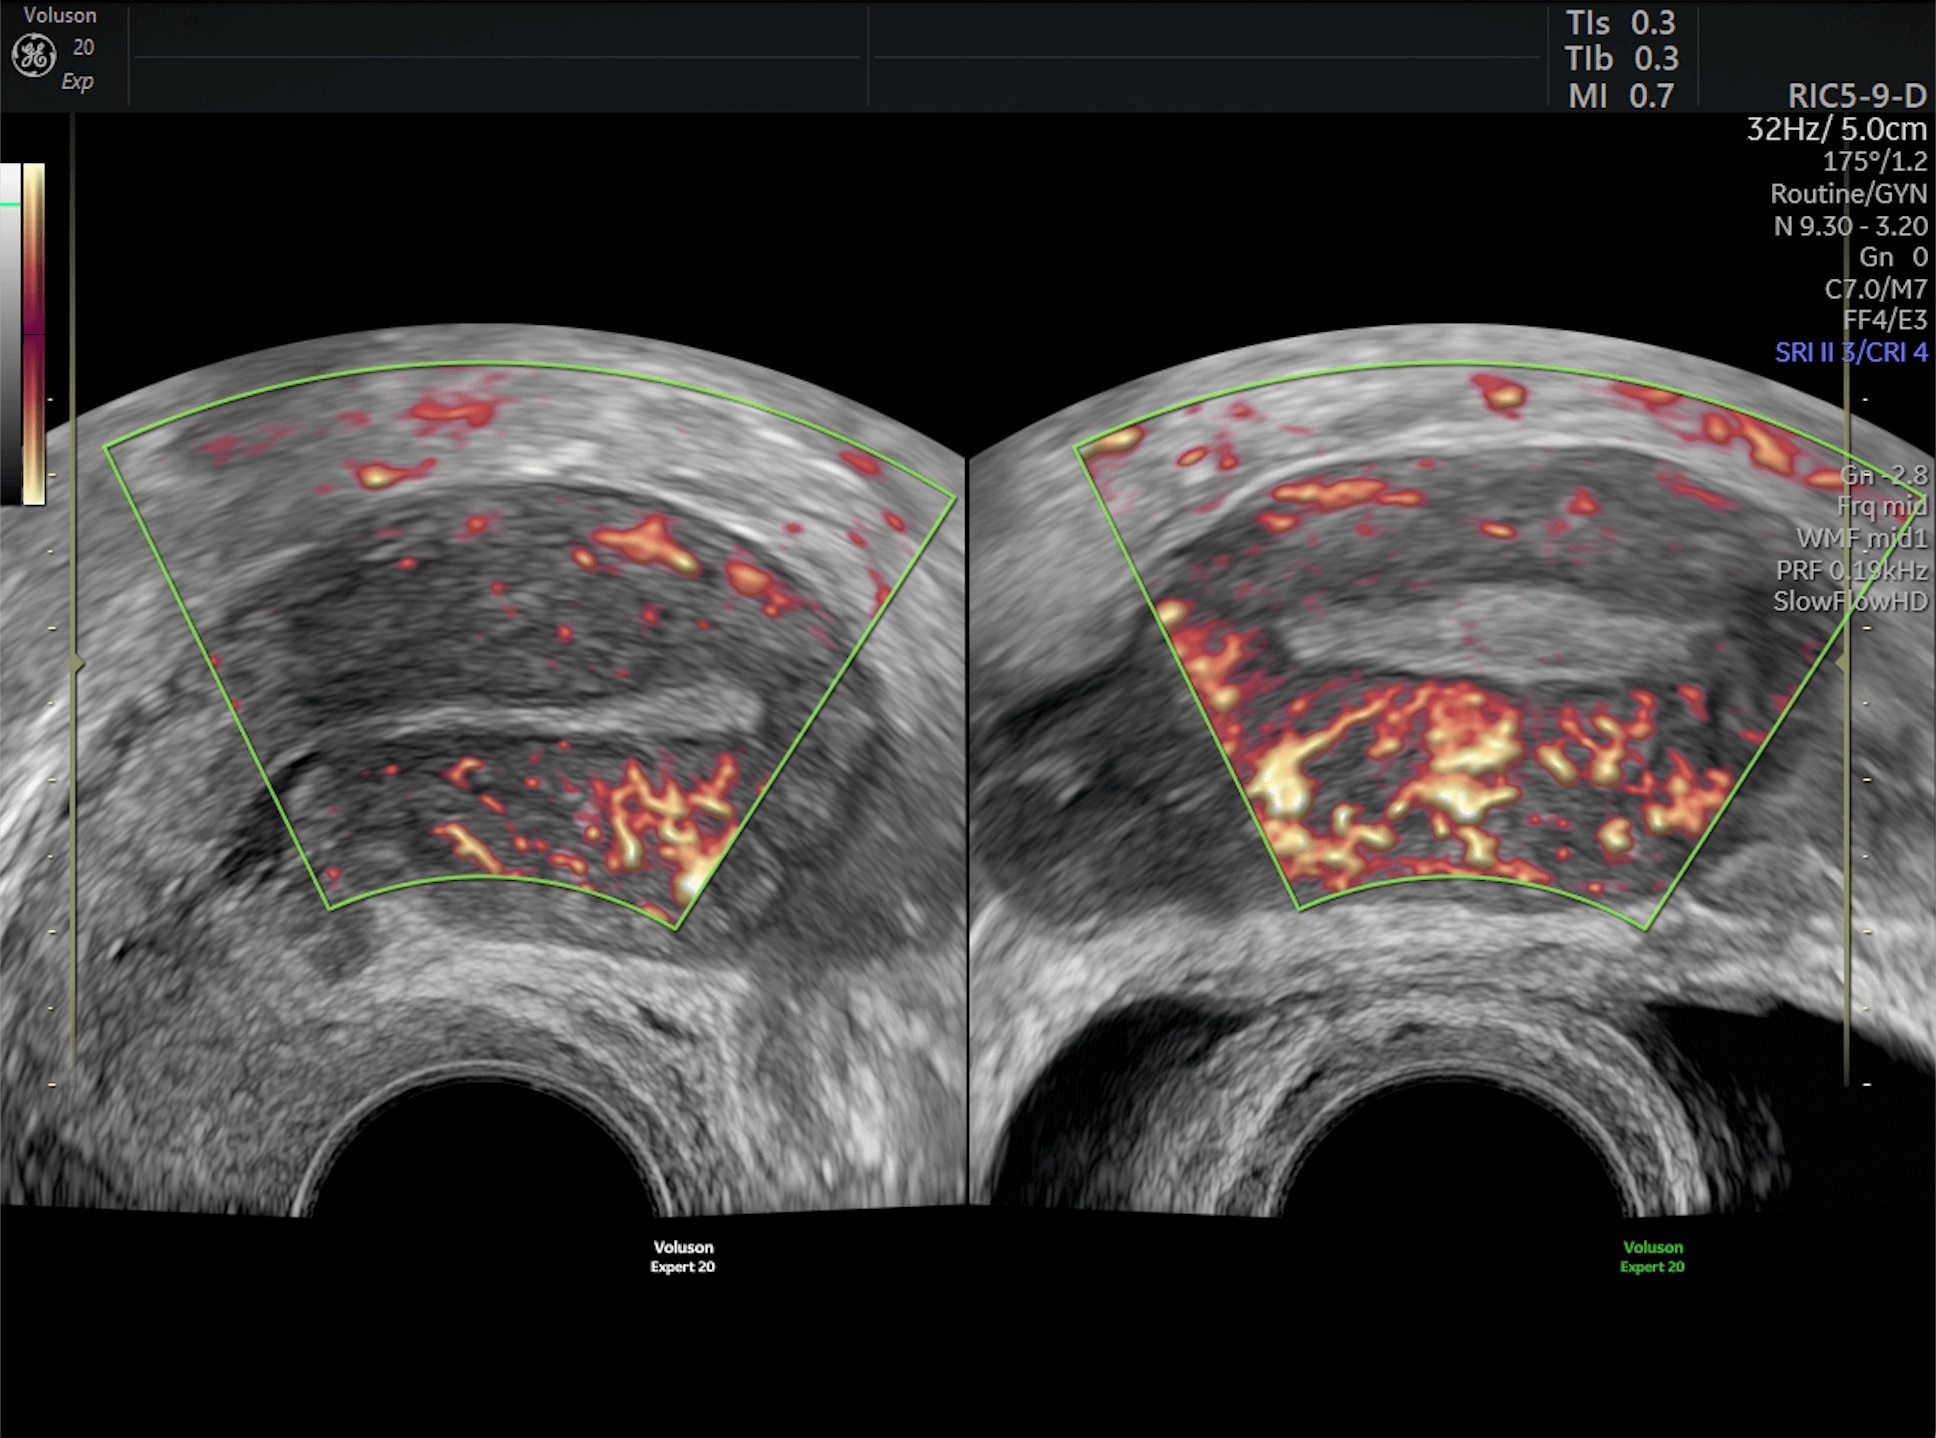

Generate spectacular 2D/3D and color Doppler images with increased penetration and stunning clarity, to help visualize critical details needed for diagnostic assurance. The Lyric Architecture unlocks new imaging and processing power to expand your imaging capabilities for years to come